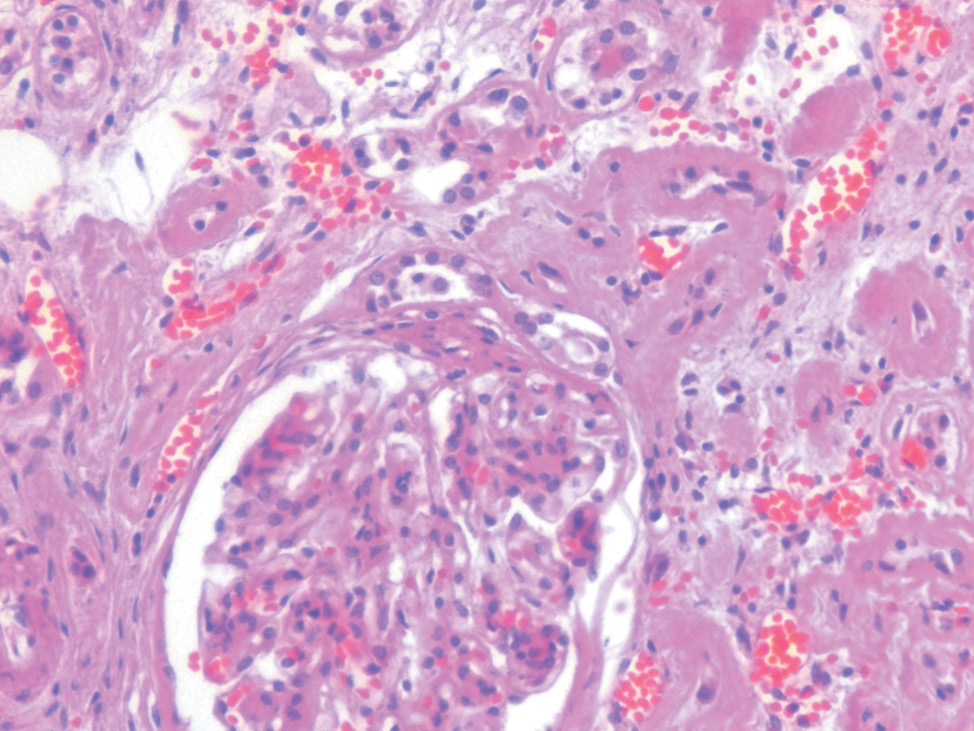

Почки: резкое нарушение архитектоники почки за счет замещения структуры стромы и клубочков фиброзной тканью с формированием рубцовых клубочков и крупных участков диффузного и очагового нефросклероза с гиалинозом и склерозом стенки артериол, с резко выраженным сужением их просвета. В единичных сохранившихся клубочках отмечается спадение петель, отложение белковых депозитов, формирование синехий и выраженное расширение мочевого пространства. Эпителий канальцев уплощен, местами некротизирован, просвет расширен, в просвете (особенно мозгового слоя) обилие крупных гиалиновых цилиндров. Артерии крупного калибра с явлениями гиперэластоза и эластофиброза, с очаговым кальцинозом (рис. 4).

Рис. 4. Почка. ×200, окраска гематоксилином и эозином. В единичных сохранившихся клубочках отмечается спадение петель, отложение белковых депозитов, формирование синехий. Эпителий канальцев уплощен, местами некротизирован, просвет расширен. Артерии крупного калибра с явлениями гиперэластоза и эластофиброза, с очаговым кальцинозом

Fig. 4. A kidney. ×200, stained with hematoxylin and eosin. In a few remaining glomeruli loops are collapsed. Also protein deposits, and formation of synechia are observed. The epithelium of the tubules is flattened, with sites of necrosis, the diameter is increased. Large caliber arteries have signs of hyperelastosis and elastofibrosis, with focal calcification